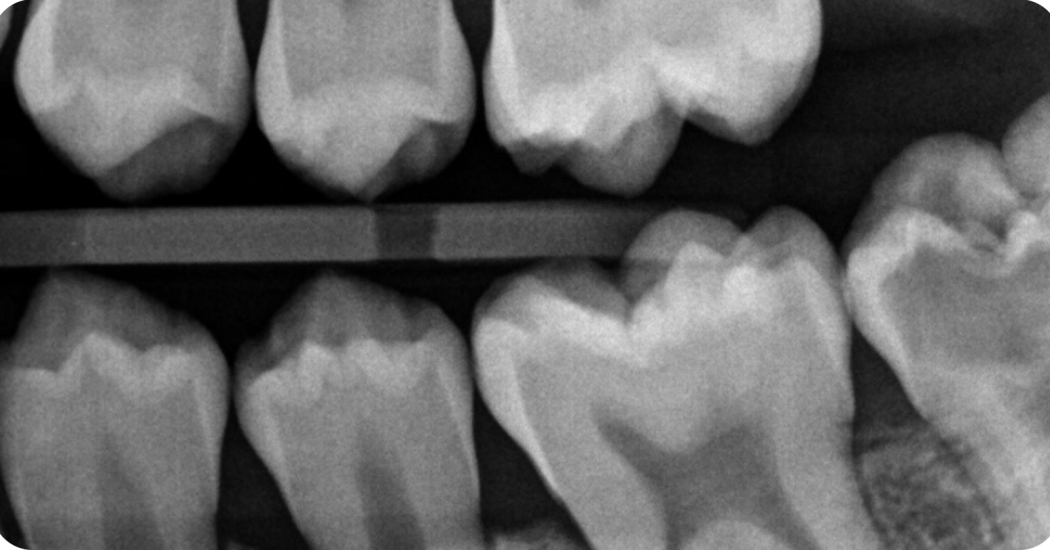

Il caso clinico presentato riguarda un bambino di 13 anni che presentava un difetto riassorbitivo non comune chiamato riassorbimento intracoronale pre-eruttivo (PEIR) e una carie che comprometteva il secondo molare inferiore. È stata eseguita una terapia pulpare vitale per conservare il dente e mantenere lo sviluppo della radice.